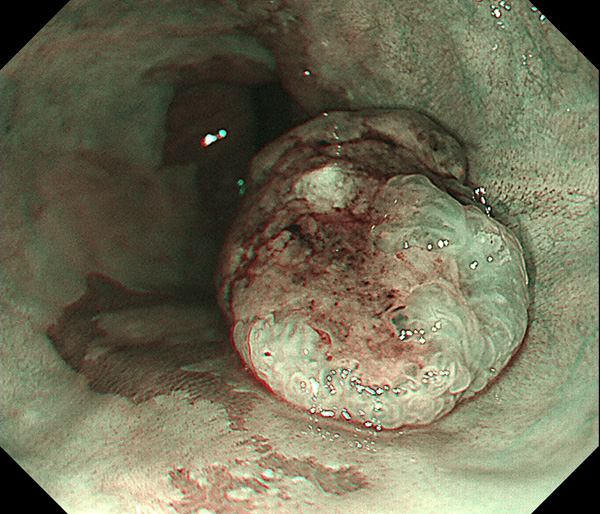

内視鏡所見と病理組織像の1対1対応が可能な症例を公募いたします。主にLSBEに発生した早期癌(HGDを含む)を対象としますが、興味深い症例であればSSBE癌でも結構です。採否は世話人へご一任ください。

症例呈示希望者は応募用紙に記入の上、代表的な内視鏡(2枚)、切除標本(新鮮、固定)、切り出し図、マッピング、代表的組織像とともに、Barrett 食道研究会事務局 barrett.shinshu@gmail.comへお申し込み下さい(10MB以下でお願い致します)。

特に、本邦では極めて稀なlong segment Barrett’s esophagus(LSBE)から発生した早期癌は、診断に難渋する場合も多く、欧米ではランダム生検による検出が標準的とされています。背景のBarrett食道もろとも全体を内視鏡切除+ラジオ波焼灼する欧米と異なり、ESDで内視鏡的な局所切除が基本の本邦では、存在診断+範囲診断(特に水平)を的確に行うことが不可欠です。

そのためには、一流の病理医による組織学的診断とエキスパート内視鏡医による拡大内視鏡像との一対一対応を徹底的に行うことで、『本来、見えないであろう拡大所見の先にある組織構築像が診えてくる』所まで内視鏡診断レベルを上げていく必要があります。その実現には、一対一対応を追究した症例(特にLSBE発生例)1例でも多く経験するしかありません。本研究会でBarrett食道腺癌(LSBE発生早期病変)を共に学び、拡大内視鏡像の一歩先を診るスキルを習得しましょう!一人でも多くの皆様のご参加をお待ちしています。